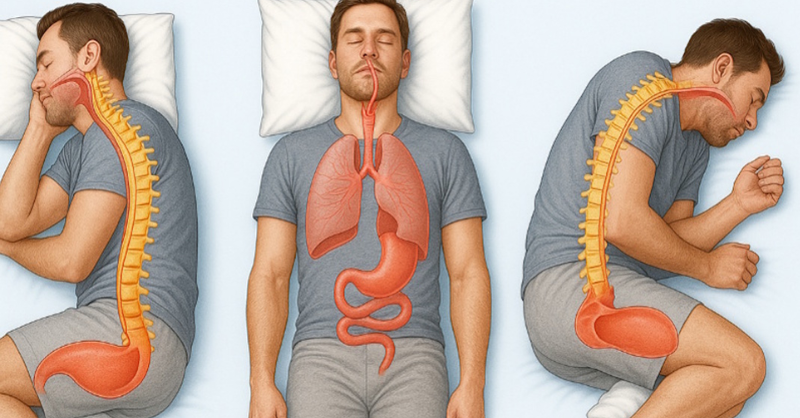

How Your Sleeping Position Affects Your Health

Every night, we crawl into bed hoping for a good, restorative sleep. On your back, on your side, curled up, or face-down—everyone has their favorite position. But have...